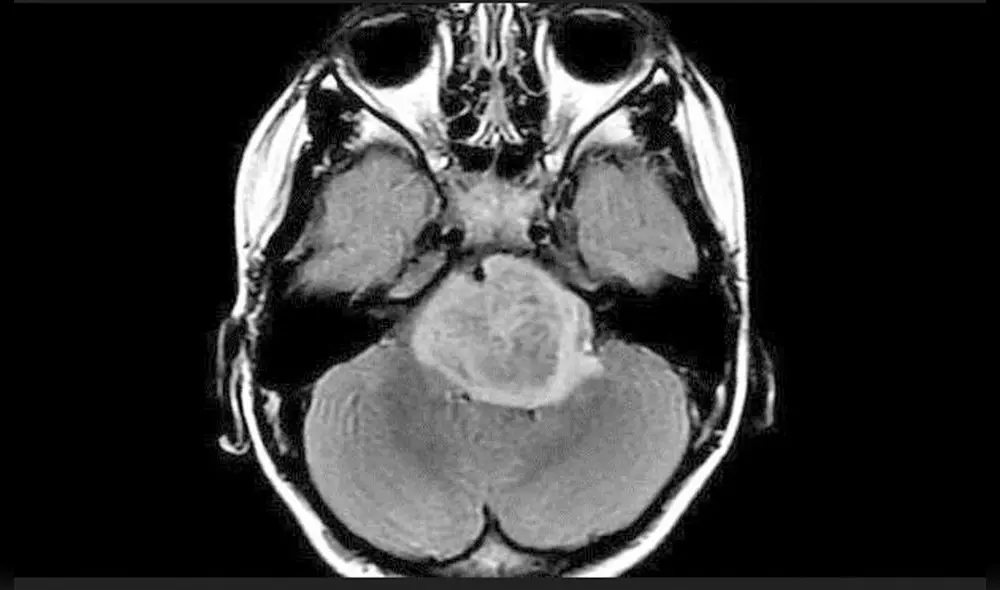

Un nuevo tratamiento ha generado esperanza para los niños que sufren glioma pontino intrínseco difuso (DIPG), un extraño cáncer cerebral agresivo que provoca la muerte en solo unos meses. Se trata de la combinación de dos fármacos empleados para otros cánceres existentes que ha mostrado eficacia ante esta enfermedad incurable.

La combinación de fármacos consta de dasatinib para la leucemia y trametinib para el melanoma. Su acción conjunta fue probada en ratones y se demostró que retarda el crecimiento de los tumores DIPG. Dicha técnica “tuvo un efecto mucho mayor de lo esperado al sumar ambos medicamentos (que si se hubiera aplicado por separado)”, detalló Jones.

El resultado fue realmente prometedor, ya que redujo el crecimiento de células cancerosas DIPG cultivadas en tejido cerebral de ratón en más de un 60%.